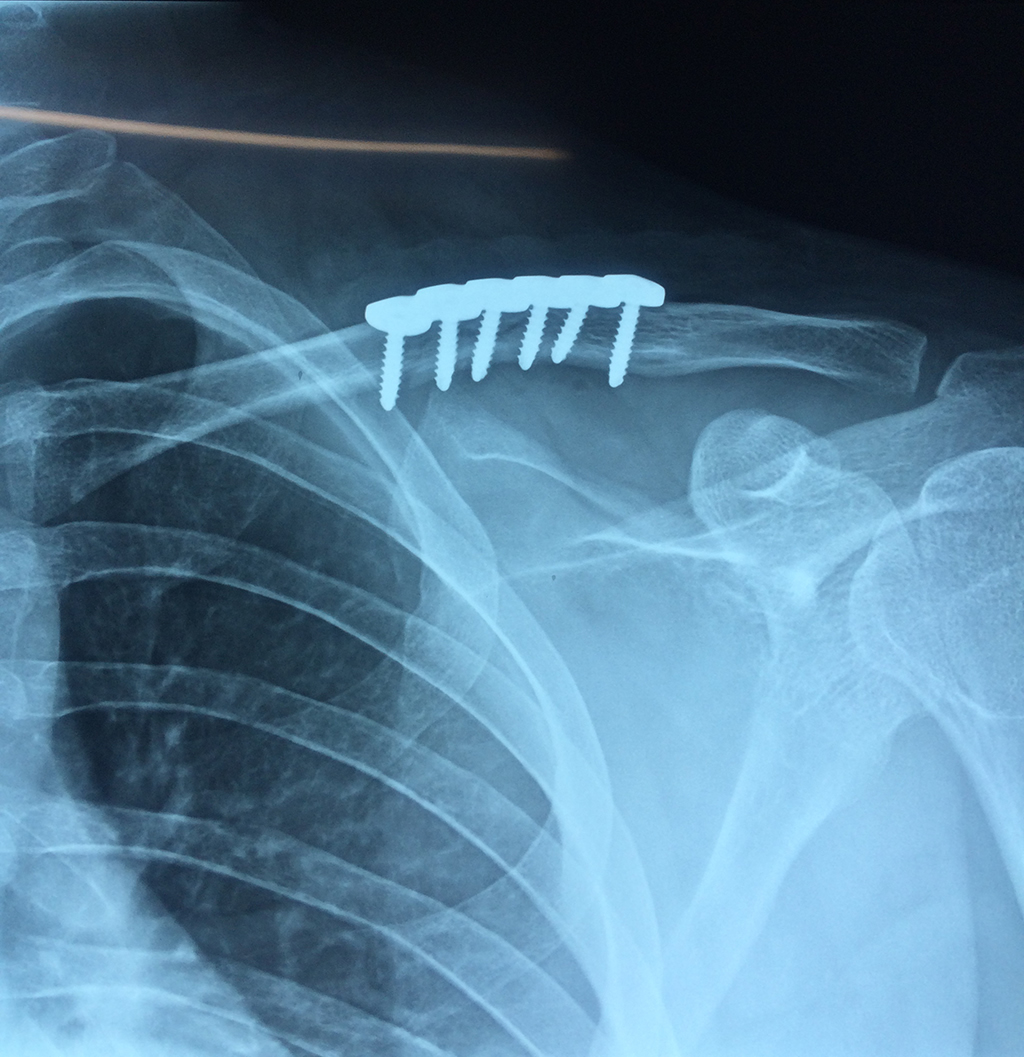

Cirugías de Codo - Clavícula

La clavícula es un hueso largo, con forma de "S" itálica, situado en la parte anterosuperior del tórax. Junto con la escápula forman la cintura escapular. Se puede palpar por toda su longitud y se extiende del esternón al acromion de la escápula, siguiendo una dirección oblicua lateral y posterior.

Se considera el único medio de unión entre el miembro superior y el tórax. A pesar de su aspecto, similar al de un hueso largo, posee una estructura semejante a la de un hueso plano, ya que carece de epífisis y de diáfisis, lo que la harían entrar dentro de la clasificación de hueso largo. Carece de un canal medular propiamente dicho.